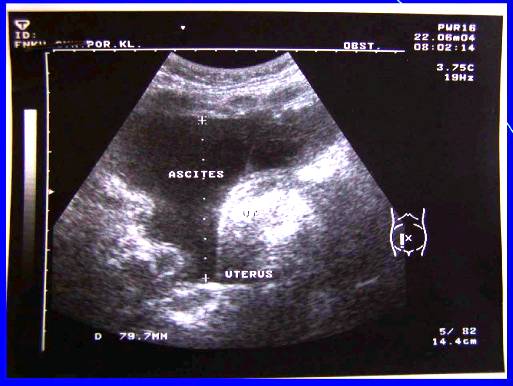

2.Recidiva (generalizace do dutiny břišní, st.p.HY a AE) pac.J.U,tu markery, punkce ascitu, cytologie

Recidiva (generalizace do dutiny břišní, st.p.HY a AE), tu markery, pac.J.U, punkce ascitu, cytologie.